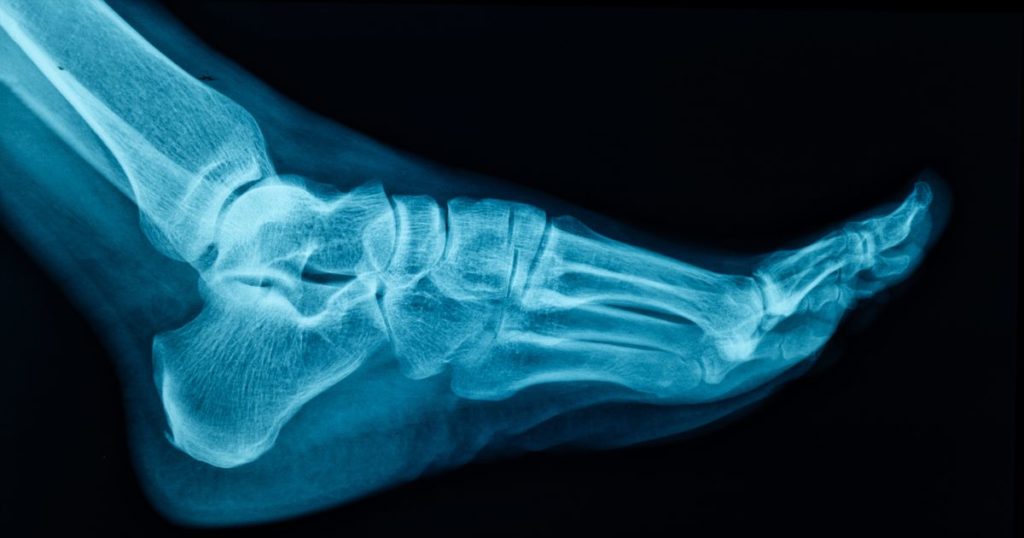

② 精密検査(レントゲン・MRI)が必要だから

事故の衝撃による骨折や脳へのダメージは、外見からは分かりません。

「ただのむちうちだと思っていたら、実は骨にヒビが入っていた」というケースもあります。

まずは医療機関で画像診断を受け、医学的に身体の状態を証明してもらうことが、今後の補償を受けるための土台となります。